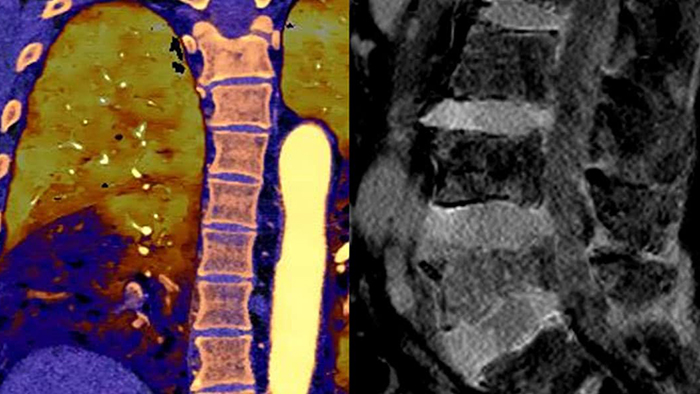

Unlike traditional CT images, spectral-detector CT images capture spectral information 100% of the time —without special planning or set-up. That means you can analyze the spectral data in any image retrospectively, using a variety of spectral viewing tools. You can, for example, adjust the monoenergetic level or get Zeffective maps.

Spectral detector simultaneously absorbs and differentiates high and low energy from a single polyenergetic X-ray beam. Spectral results are acquired within a single scan without the need for special modes.

Detector-based spectral CT simultaneously absorbs high and low energies in the same time and space.

Spectral CT helps me objectively differentiate contrast staining from hemorrhage, obviating the need for additional follow up scanning and prolonged patient observation, which can result in reduced costs and radiation exposure to patients.1,2